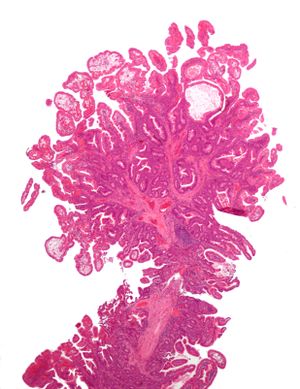

السليلة | الظهور النسيجي | خطورة الخباثة | صورة | المتلازمات |

---|---|---|---|---|

Hyperplastic | Serrated unbranched crypts | لا | Hyperplastic polyposis syndrome | |

Sessile serrated adenoma | Similar to hyperplastic with hyperserration, dilated/branched crypt base, prominent mucin cells at crypt base | نعم | ||

Inflammatory | Raised mucosa/submucosa with inflammation | If dysplasia develops | Inflammatory Bowel Disease, ulcers, infections, mucosal prolapse | |

Tubular Adenoma (Villous, Tubulovillous) | Tubular glands with elongated nuclei (at least low-grade atypia) | نعم | ||

Traditional Serrated Adenoma | Serrated crypts, often villous architecture, with cytologic atypia, eosinophilic cells | نعم | ||

متلازمة پويتز-جيگرز | Smooth muscle bundles between nonneoplastic epithelium, "Christmas tree" appearance | لا | متلازمة پويتز-جيگرز | |

سليلة الشباب | Cystically dilated glands with expanded lamina propria | Not inherently, may develop dysplasia | Juvenile polyposis syndrome, identical polyps in Cronkhite-Canada syndrome | |

Hamartomatous Polyp (Cowden Syndrome) | Variable; classical mildly fibrotic polyp with disorganized mucosa and splaying of muscularis mucosae; also inflammatory, juvenile, lipoma, ganglioneuroma, lymphoid | لا | متلازمة كاودن | |

Inflammatory fibroid polyp | Spindle cells with concentric arrangements of spindle cells around blood vessels and inflammation rich in eosinophils | لا |